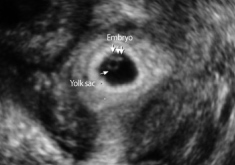

Definite IUP = gestational sac containing yolk sac

- Occurs ~5.5th week

- MUST contain yolk sac to be confirmed IUP. Pseudogestational sac possible in ectopic pregnancy